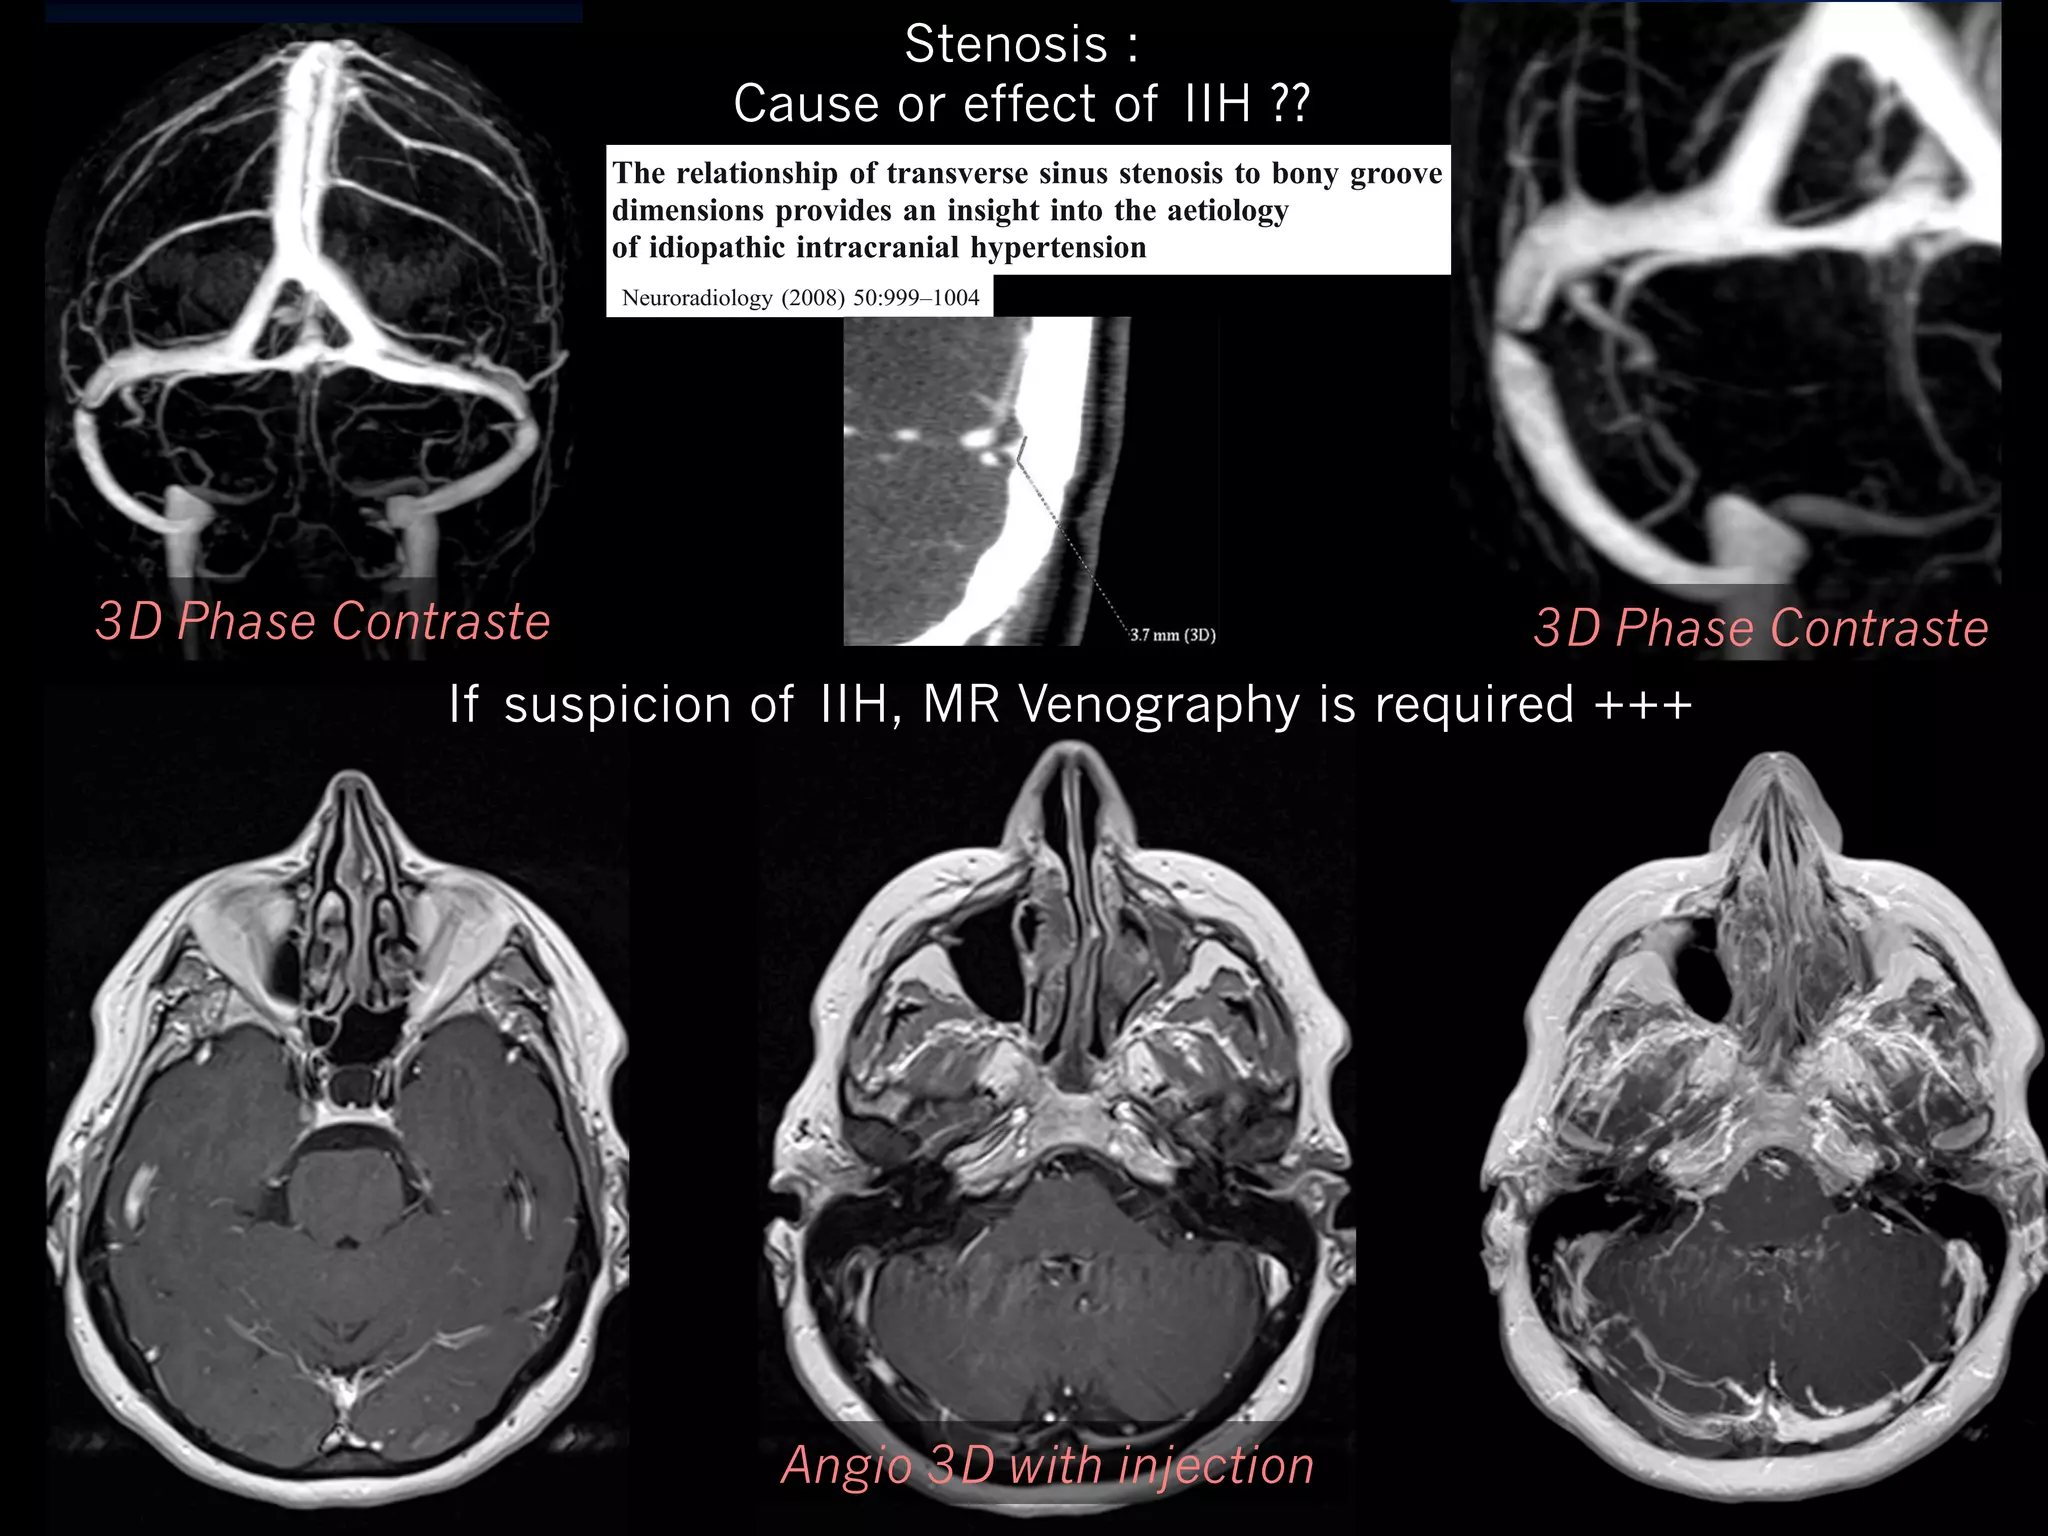

Stenosis :

Cause or effect of IIH ??

Neuroradiology (2008) 50:999–1004

of idiopathic intracranial hypertension

3D Phase Contraste

If suspicion of IIH, MR Venography is required +++